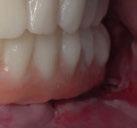

Exploración Intraoral

Presenta un estado oral deficitario. Parcialmente edéntula, con colapso de mordida, migración dental patológica, restauraciones de resina antiguas fisuradas y filtradas, transparencia y exposición de cámara pulpar secundaria a desgastes con pérdida de estructura e integridad de tejido dental importante (Figuras 1 a 4). Portadora a tiempo parcial de prótesis removibles desadaptadas de más de 10 años de antigüedad, refiriendo incapacidad de adaptación a este tipo de prótesis.

Se constata reducción del tercio facial inferior produciendo a nivel estético una apariencia envejecida por formación de surcos en las comisuras labiales («líneas de marioneta») secundarias a una disminución de la dimensión vertical por desgaste dental (Figuras 5 y 6).